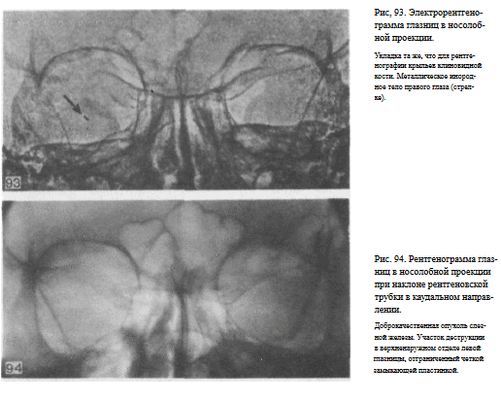

В качестве примера информативности снимка глазниц в носолобной проекции для выявления инородных тел глаза и деструктивных изменений стенок приводим два наблюдения.

Одно из них — случай ранения глаза металлической стружкой (рис. 93), другое — случай деструкции верхненаружного края глазницы при доброкачественной опухоли слезной железы (рис. 94).